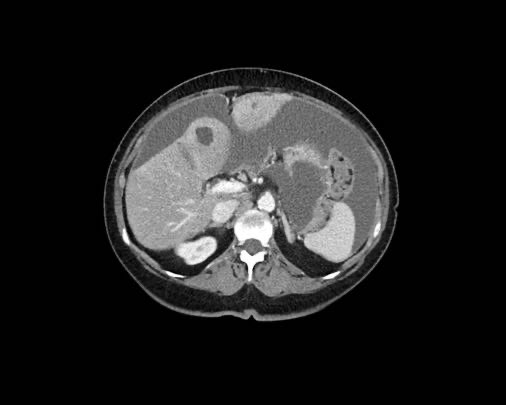

Ca lâm sàng 1

Cuộn qua các lát cắt.

Bạn có thể phát hiện tất cả các tổn thương cấy ghép phúc mạc không?

Bệnh nhân này đã được phẫu thuật và toàn bộ phúc mạc được ghi nhận phủ kín bởi các tổn thương u dạng kê.